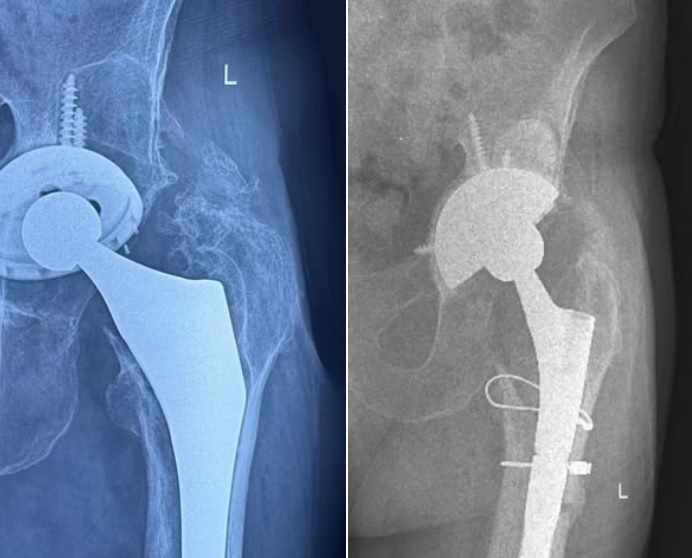

Echipa medicală condusă de către medicul ortoped Bogdan Niculescu, fostul șef al Secției de Ortopedie din Cadrul Spitalului Județean de Urgență Târgu Jiu, a operat un pacient de 87 de ani, pentru înlocuirea unei proteze de șold. Operația a avut loc în Timișoara, iar pacientul fusese respins de mai multe spitale din cauza riscurilor care pot să survină ca urmare a vârstei înaintate:

Am luat decizia de a efectua înlocuirea protezei existente cu o proteză de revizie-Tantal poros (Trabecular Metal) si stem Revitan, iar intervenția a decurs fără complicații. Recuperarea a fost bună, iar la 6 luni de la operație, domnul Marin și-a recăpătat mobilitatea și normalitatea vieții de zi cu zi.